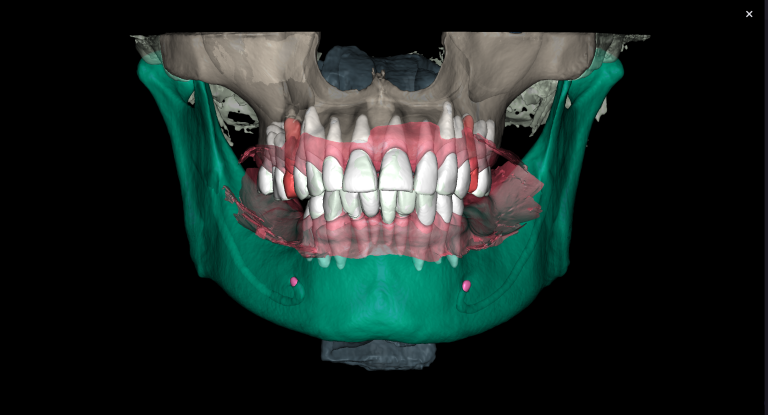

We start by loading the intraoral scan data into the Diagnocat STL module and getting a 3D model for choosing the optimal spatial position of the implant and planning the virtual design of the template for guided implant surgery